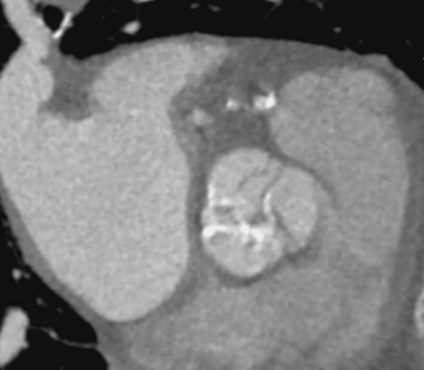

TAVI術前の拡張期の画像です。

モーションアーチファクトが抑制され、石灰化評価や計測がしやすい画像となっています。